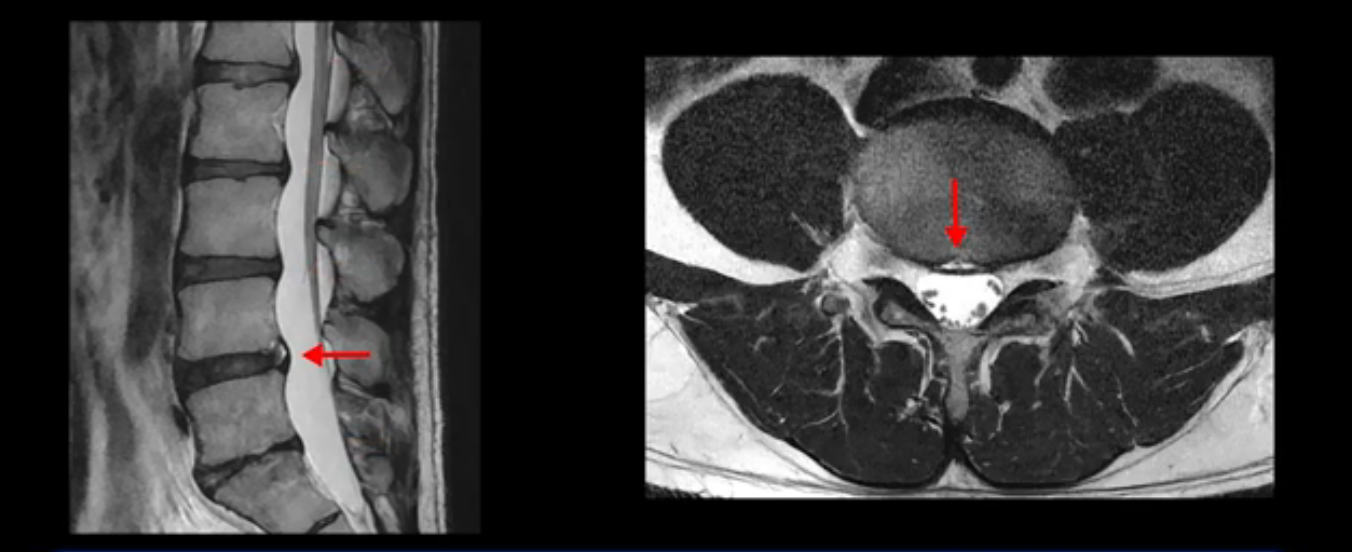

4번 5번은 가운데로 섬유륜이 찢어져서 디스크가 살짝 밀려나와 있지만 역시나 최근에 찢어지고 밀려나온 걸로 판단되지 않고 오래 전에 찢어진 흔적으로 보입니다.

앞서 1번 2번, 4번 5번, 5번 1번의 디스크가 찢어지고 조금 밀려 나온 게 최근에 찢어진 게 아니고 오래된 걸로 보인다고 말씀 드렸죠. 왜 그럴까요? 만약 급성으로 찢어진 것이라면 아주 심한 디스크성 통증이 있겠죠. 기침이나 재채기를 하면 심하게 아프고 허리를 조금만 구부리거나 비틀면 아주 날카로운 통증들이 생길 겁니다. 그런데 이분은 이런 증상이 전혀 아닙니다. 또 디스크의 밀려나온 정도도 전혀 심하지 않기 때문에 이분이 가지고 계신 양쪽 다리 저림, 특히 이분은 누워있을 때도 양쪽 발이 발가락까지 쑤신다고 하는데 이정도 디스크 때문에 그런 증상은 생길 수가 없는 겁니다. 이처럼 이분의 가벼운 디스크 탈출은 이미 오래 전에 진행되었고 섬유륜 자체는 이미 아문 상태인데도 디스크내장증을 진단받은 환자들 중에는 본인이 섬유륜 파열 환자라고 끝까지 믿는 분들이 많습니다. 다시 말하지만 디스크내장증이라는 진단을 받은 환자들을 보면 거의 전부 다 섬유륜 파열 증상이 아닙니다. 증상이 완전히 다릅니다. 진단이 애초에 잘못되면 어떤 치료를 받아도 좋아질 수 없습니다.

이분은 어떤 한 병원에서 디스크 내장증 얘기를 들으셨는데요. 여기 보시는 것처럼 4번 5번의 하얀 HIZ(High Intensity Zone)을 보고 디스크 내장증의 근거로 얘기하는 병원들이 있는데,

이 HIZ는 섬유륜이 찢어졌다가 이미 아문 뒤에도 얼마든지 보일 수 있는 흔적일 가능성이 있어서 재채기를 하면 아픈지, 허리를 구부릴 때 날카로운 통증이 생기는가 등의 증상으로 구별해야 하는데 MRI만 보고 HIZ가 보이면 그게 마치 통증의 원인인 것처럼 얘기하는 의사들이 있습니다. 이분 MRI를 자세히 보고 증상을 정말 자세히 들어본 의사가 있었더라면 다른 환자분들처럼 증상과 MRI가 일치하지 않는다는 얘기를 들을 수 있었을 텐데 이분은 그런 얘기는 듣지 못했습니다.